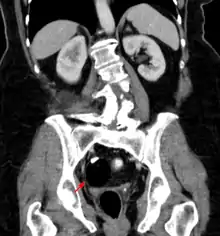

ورم مسخي للمبيض